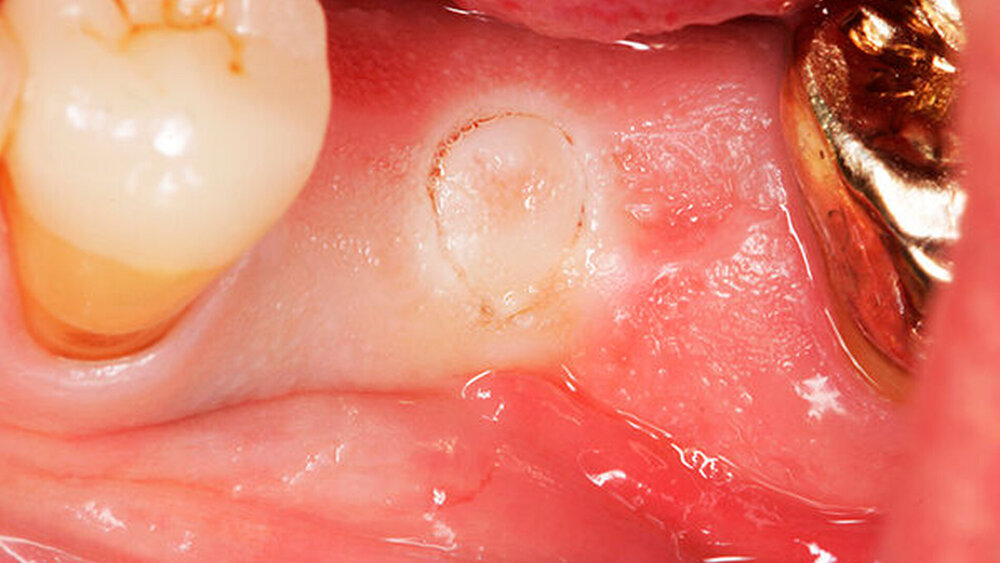

Die größte Herausforderung dabei, trotz 3D-Planung und Bohrschablone, ist es, die rote Ästhetik im Frontzahnbereich zwei bis drei Monate nach der Freilegung vorhersagbar zu kalkulieren. Da spielen viele Einflussfaktoren eine Rolle, eine zu dünne vestibuläre Knochenlamelle, der Stressfaktor „axiale Bewegung“, der diese dünne Knochenlamelle schnell überfordern kann etc. Zieht sich das rosafarbene Volumen zurück, ist das natürlich für den Zahntechniker schwierig zu handeln. Eine rosafarbene Gingivakappe, die aus Keramik aufgebrannt wird, kann helfen. Das ist zwar ein Kompromiss, aber ein Kompromiss, mit dem die Patienten leben können.

Was wäre die Alternative?

Wilde:

Aufwendige Augmentationen. Nach umfangreichen Knochendefekten im anterioren Bereich müsste der Knochen aufgebaut werden, Bindegewebstransplantate etc. verbessern die Situation weiter. Doch Patienten möchten irgendwann auch einmal die Behandlung abschließen. Und Zahntechniker meistern die keramische Gingivakorrektur wirklich großartig. Auch wenn es für den Behandler wenig zufriedenstellend ist, es gilt mit adäquatem Aufwand ein gutes Ergebnis zu erzielen.